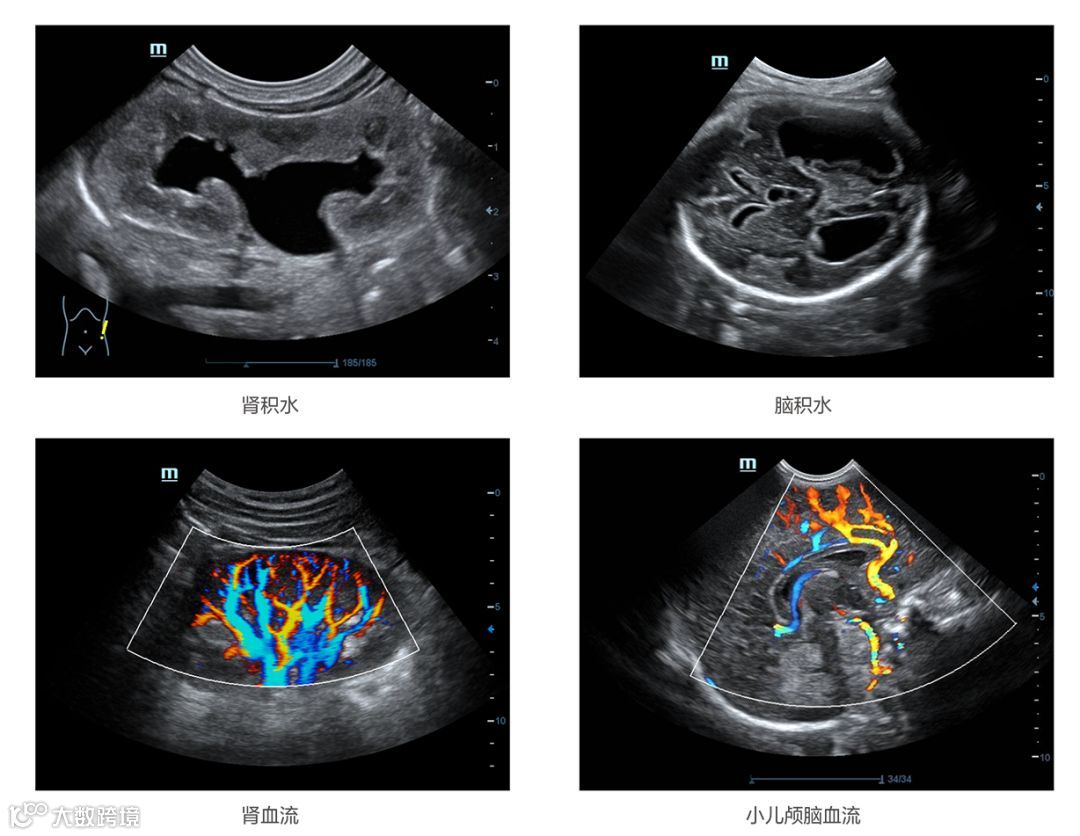

GE超声目前三大产品线Logiq系列,Voluson系列,Vivid系列,型号齐全,产品丰富。尤其以妇产的Voluson系列产品最为经典,从Voluson 730开始,到E8,再到目前的E10。但凡新的产品推出,都能在全球掀起一阵GE妇产旋风,受欢迎程度可见一斑。

目前迈瑞公司的产品线非常齐全,在收购了美国Zonare公司之后,2016年又推出了Resona系列的高端产品,打破了进口品牌在高端彩超的垄断。迈瑞的便携式彩超近几年一直占据着这一细分领域的销售龙头。目前除了专业的高端心脏彩超还没有涉及,其他的彩超技术领域几乎都已经突破。是业内除GE之外,产品线最齐全的厂家。